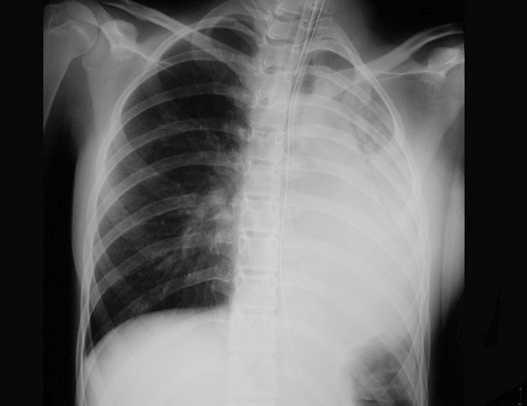

Se presenta el caso de una niña de 13 años con cuadro agudo de estridor y dificultad respiratoria; la radiografía de tórax fue normal. La laringoscopia únicamente demostró abundantes secreciones. Se trasladó a nuestra UCIP en situación de insuficiencia respiratoria aguda, precisando ventilación mecánica no invasiva. El análisis de sangre al ingreso fue anodino; radiografía lateral de cuello y ecografía cervical normales. En la radiografía de tórax de control apareció pequeño infiltrado basal izquierdo por lo que se diagnosticó neumonía y se inició tratamiento con corticoides y cefotaxima; la paciente mejoró rápidamente. A las 72 h tras el alta la niña presentó disfagia y alteración de la fonación, junto a reaparición de hipoxemia grave. Precisó intubación y ventilación mecánica invasiva convencional. La radiografía de tórax mostraba atelectasia masiva del pulmón izquierdo (fig. 1). La fibrobroncoscopia mostró abundantes secreciones sin otros hallazgos. No aparecieron leucocitosis ni elevación de la proteína C reactiva y los cultivos de sangre y lavado broncoalveolar fueron negativos.

Figura 1. Atelectasia de pulmón izquierdo.